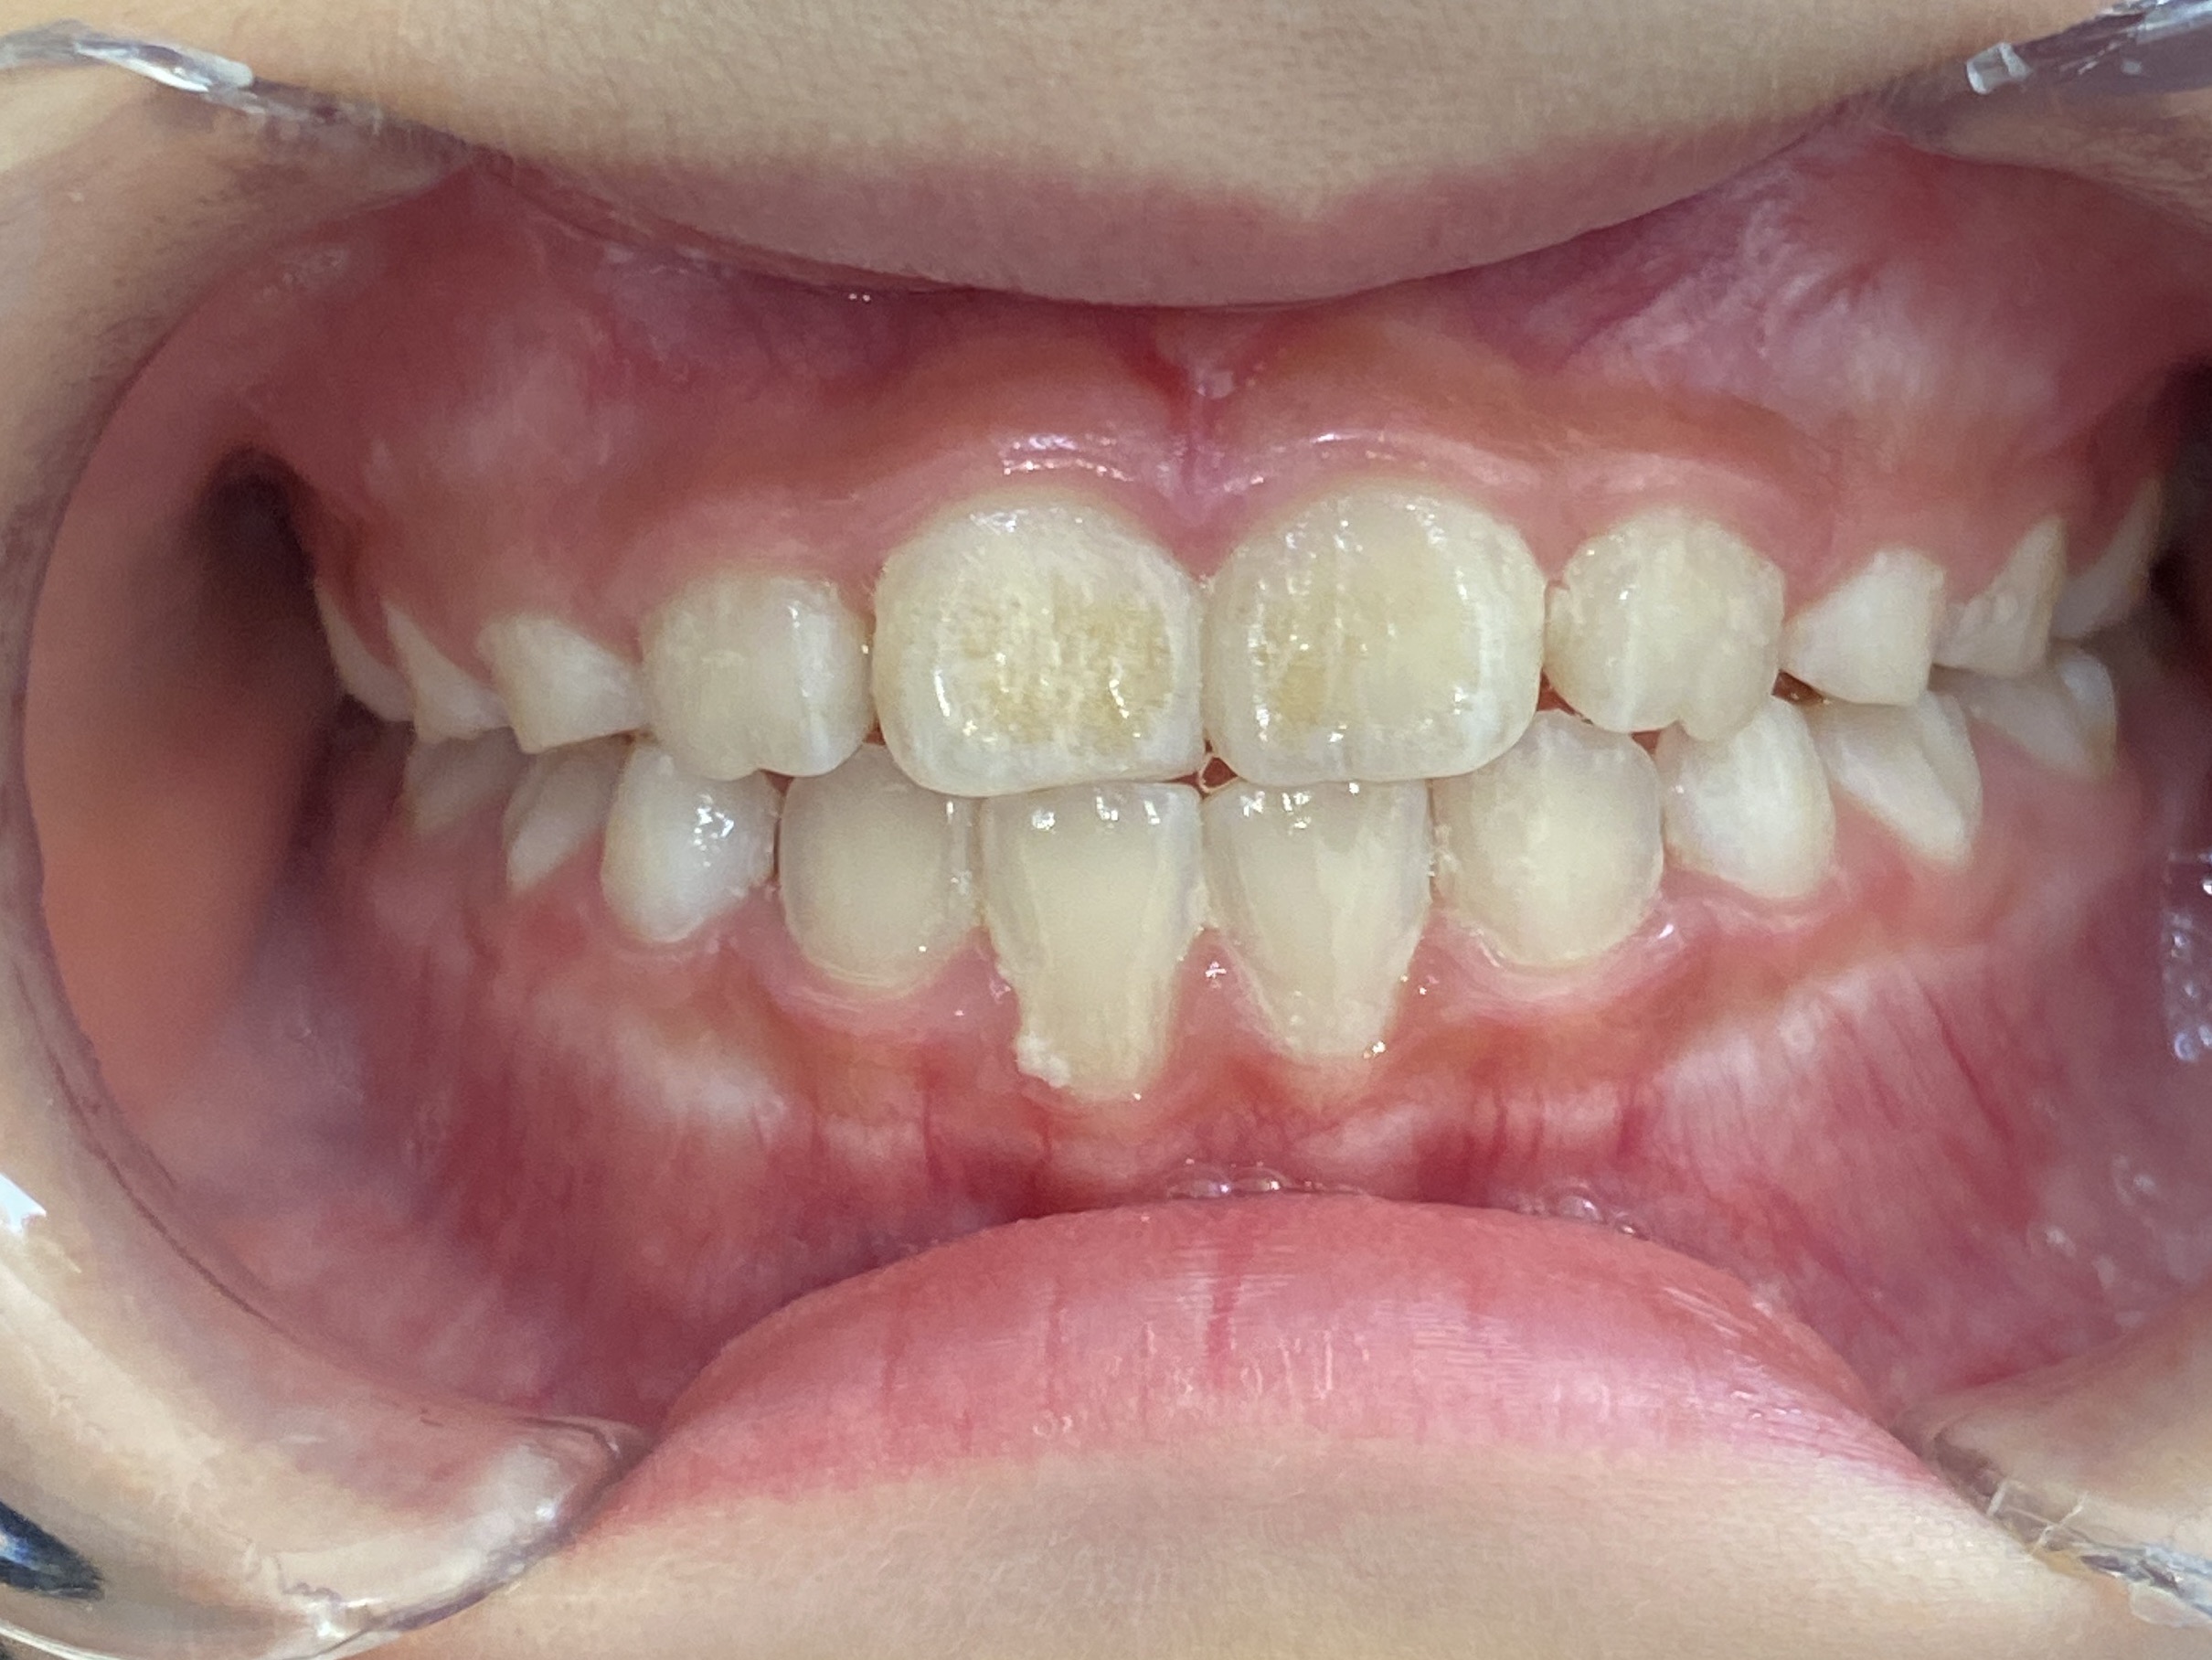

拝見すると、上下の前歯同士が噛み合っている「切端咬合(せったんこうごう)」と、前歯から奥歯までの歯並びが狭くなっている「歯列弓の狭窄(しれつきゅうのきょうさく)」の状態でした。そのため、将来ガタガタの歯並び「叢生(そうせい)」になることが予想できました。

切端咬合は放置しておくと、下顎の成長により下の前歯が上の前歯よりに前に出てしまう噛み合わせ「反対咬合」になってしまうおそれがあります。